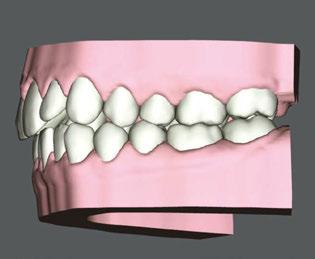

Clear Aligner Therapy (Figures 7, 8, 9)

Our orthodontic goals were the following:

1. Expand upper arch, correct crossbite

2. Close anterior open bite

3. Correct crowding

Patient J was prescribed a series of 43 aligners, with each aligner being worn for 20 hours a day for 1 week.

This comprehensive approach combining aligner therapy and MFT aimed to correct oral dysfunction, enhance breathing patterns, and ensure the long-term stability of orthodontic treatment. It combined clear aligners with MFT to address both the esthetic and functional aspects of the patient’s oral health.

Figure 7: Digital view of right side before treatment

Figure 8: Digital anterior view before clear aligner treatment

Figure 9: Digital view of left side before treatment. Anterior open bite